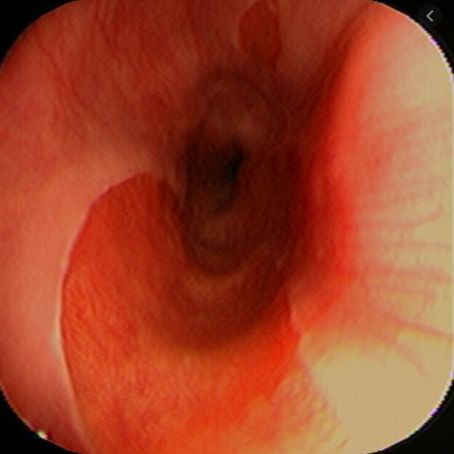

Việc phát hiện các tổn thương giống cấu trúc niêm mạc dạ dày lạc chỗ và xác nhận sau đó bằng mô học sẽ giúp tránh nhầm lẫn giữa ung thư sơ bộ với niêm mạc dị vật. Các cấu trúc niêm mạc dạ dày lạc chỗ xuất hiện với vùng tiêu điểm màu đỏ hoặc hồng cá hồi trên nội soi tiêu chuẩn và là một tổn thương màu nâu sẫm đồng nhất được phân tách rõ ràng với biểu mô vảy màu xanh lục nhạt ở chế độ NBI .

6. Vai trò của hệ thống hình ảnh dải hẹp NBI

Hệ thống NBI có thể rất hữu ích để xác định các khu vực màu nâu với các chấm màu nâu và các mạch phân nhánh trong thực quản cổ là ung thư thực quản bề ngoài tiềm ẩn. Do đó, việc áp dụng kết hợp phóng đại và NBI có thể giúp thông báo và chỉ đạo việc quản lý chẩn đoán và phát hiện sớm ung thư thực quản. Nội soi phóng đại với hệ thống NBI ưu việt hơn nội soi ánh sáng trắng thông thường trong việc phát hiện ung thư sớm và giúp giải quyết các mô vi mạch của bề mặt niêm mạc thực quản. Một cách lý tưởng, có thể triển khai trong tương lai hệ thống phát hiện tự động ung thư sớm tương tự như thuật toán máy tính tự động được phát triển cho u tân sinh sinh ở thực quản Barrett do Fons van der Sommen và cộng sự đề xuất

Có thể có các yếu tố nguy cơ đồng thời khác có liên quan. Tuy nhiên, xem xét rằng ung thư trong các cấu trúc niêm mạc dạ dày lạc chỗ thường được báo cáo là các trường hợp cá biệt, cần tập trung vào khả năng phân biệt chính xác giữa các cấu trúc niêm mạc dạ dày lạc chỗ vô hại và các khối u ác tính bề ngoài. Vì nội soi ánh sáng trắng có thể không tiết lộ các đặc điểm bất thường của ung thư sớm, nên việc sử dụng thường quy nội soi thực quản ảo trong thực quản là chính đáng. Việc báo cáo sai tỷ lệ cấu trúc niêm mạc dạ dày lạc chỗ bằng nội soi phải được tránh và các nghiên cứu trong tương lai nên được thực hiện để đưa ra các kết luận thích hợp hơn.